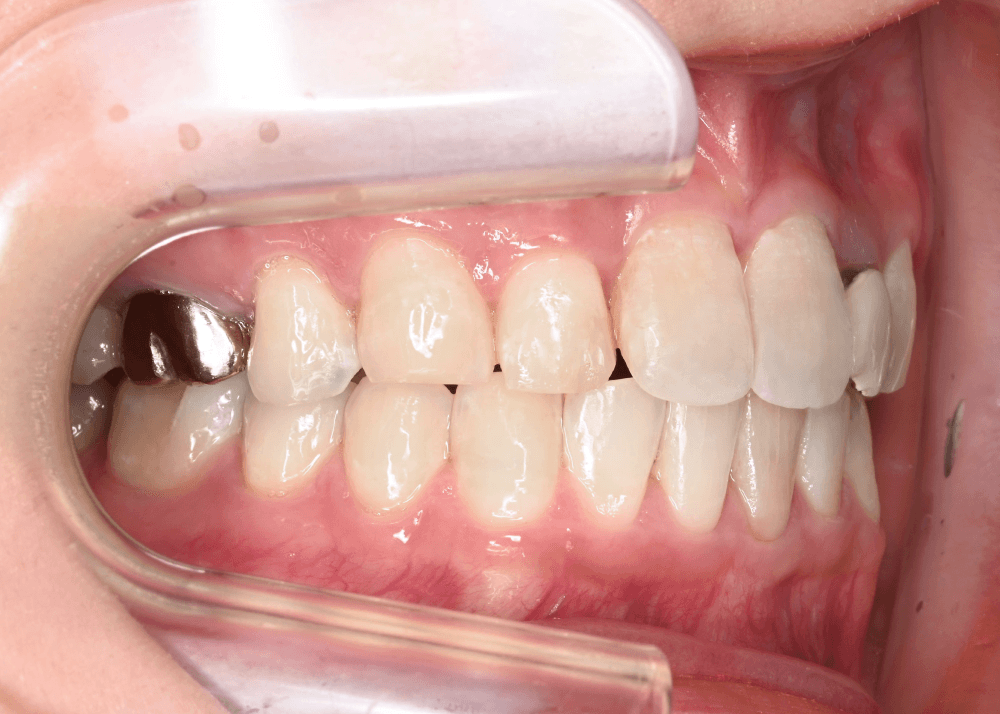

治療後の変化

治療後は、舌側に倒れていた前歯の傾きが改善しています。

・上下前歯のなす角(Interincisal angle)

138° → 125°

前歯のポジションが適正化されたことで、スマイル時に奥まって見えていた歯の見え方が改善し、より自然な印象になっています。

また、唇を内側から支える「口唇サポート」が回復し、横顔の印象にも変化がみられました。

治療前後の写真比較

治療後(32か月)